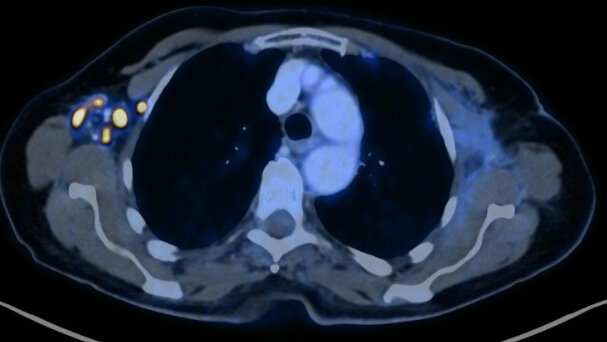

Amazing how intense axillary lymph nodes react after

#COVID19#vaccination. Patient received her 2nd#mRNA shot in the right deltoid 3 days before this PET-Scan without any relevant side effects.#VaccinesWorkpic.twitter.com/VSMCqcHjmp